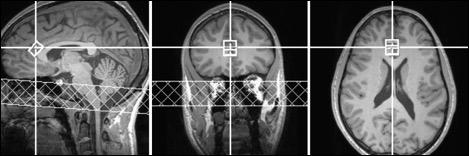

In this new study, subjects were first screened for mental and physical health and then underwent MRI spectroscopy scans designed to detect the concentration of neural compounds in specific regions of their brain. From the medical literature on psychostimulants, White and her team wanted to look in the anterior cingulate cortex, which is a "hub" brain region that connects multiple brain networks involved in emotion, decision-making and behavior.

They found that two ADHD medications, d-amphetamine and Desoxyn, significantly increased the overall amount of glutamate in the right dorsal anterior cingulate cortex, even after controlling for possible confounding factors, such as volume of gray matter in the region. The rise in brain glutamate predicted both the duration and the intensity of positive emotion, measured by participant ratings about whether they liked the drug or felt high after consuming it.